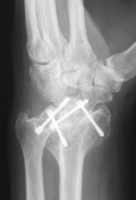

Three months postop :

Image Image Image